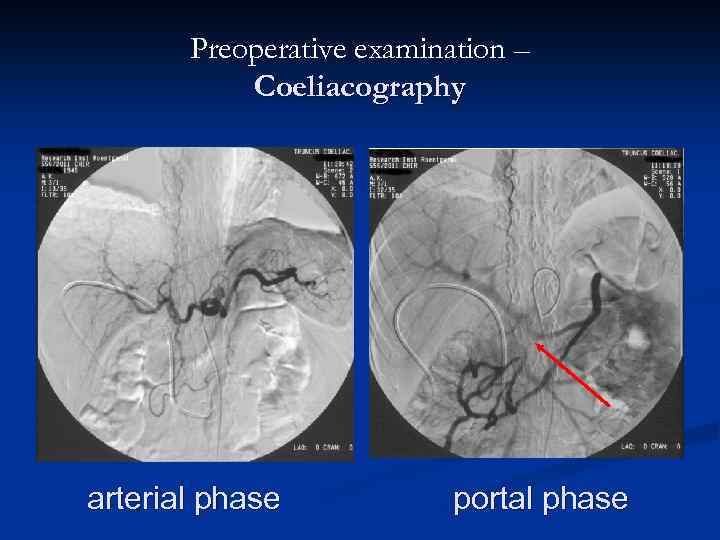

Preoperative examination – Coeliacography arterial phase portal phase

Preoperative examination – Coeliacography arterial phase portal phase